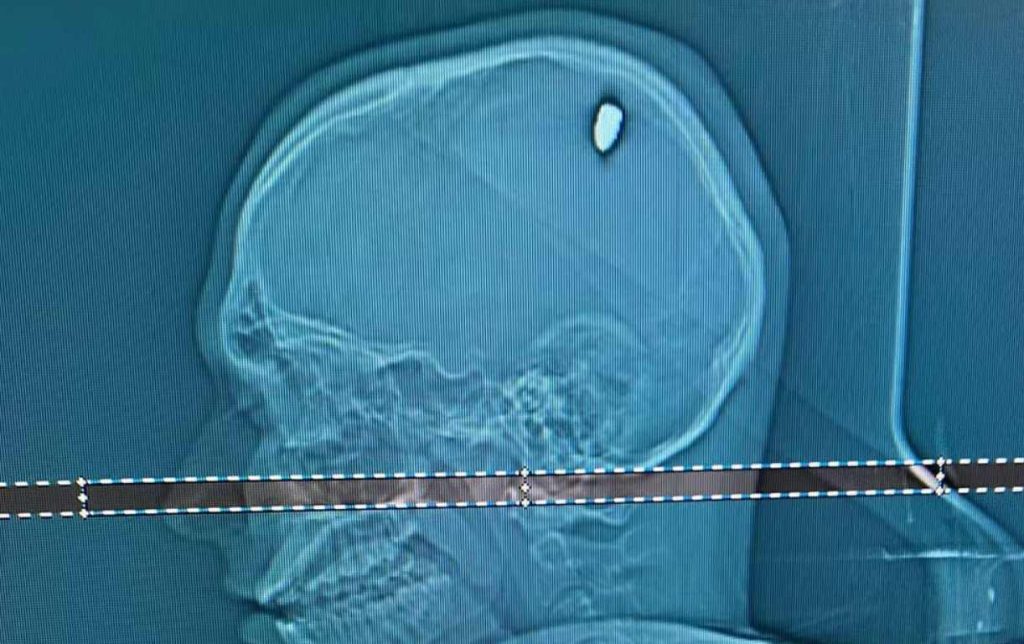

Após exames em um hospital particular de Juiz de Fora, foi identificada a bala, de calibre 9 milímetros, alojada na cabeça dele.

A cirurgia para retirada do projétil durou aproximadamente duas horas. Depois disso, ele permaneceu dois dias na CTI e mais um no quarto, até receber alta. Mateus agora se recupera em casa.